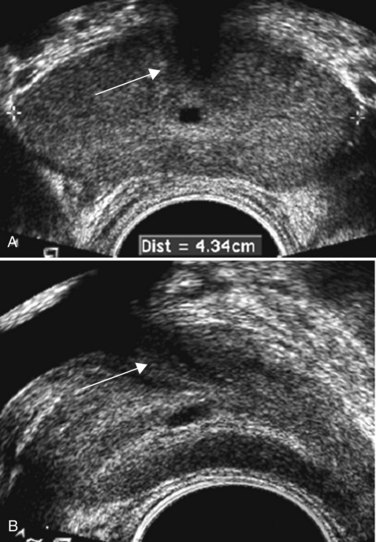

A new sonographic technique known as elastography may prove to be superior to color Doppler imaging in the identification of malignant areas in the prostate (Nelson et al, 2007; Sumura et al, 2007). This technique employs real-time sonographic imaging of the prostate at baseline and under varying degrees of compression (Fig. 97–9). Through computerized calculations, differences in displacement between ultrasonic images from baseline and during compression may be visualized, and regions with decreased tissue elasticity may be tagged as suggestive of malignancy. In a preliminary study of 404 cases, with 151 cases positive for prostate cancer, the malignancy was found in 127 patients (84.1%) with real-time elastography directing the biopsy (Konig et al, 2005).

Figure 97–9 Elastography demonstrates an area of decreased compliance in the right base consistent with an underlying malignancy (blue near arrow). Note color scale in upper right corner indicating relative tissue “firmness.” Targeted biopsy of this region revealed a Gleason 4 + 4 = 8 adenocarcinoma.